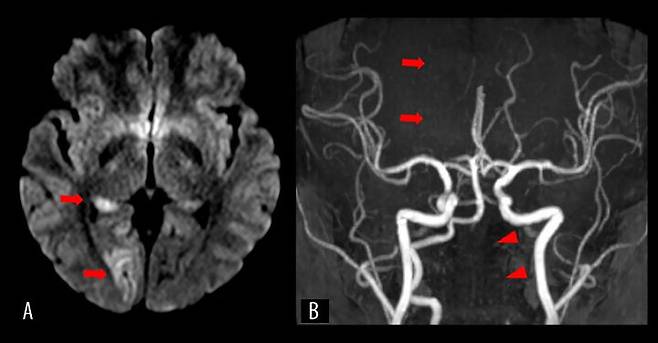

진단 결과 A씨는 격렬한 동작으로 인해 왼쪽 척추동맥 내막이 찢어지고, 이에 따라 혈액이 스며들어 혈전이 형성됐다. 이 혈전은 뇌 시각 중추로 가는 주요 혈관을 막아 허혈성 뇌졸중을 유발했다. 결과적으로 A씨는 양쪽 눈의 왼쪽 반쪽 시야를 잃고 왼쪽 반신 감각을 잃는 심각한 상태에 이르렀다.

A씨는 곧바로 혈전 제거술과 동맥 내 혈전용해술 받았으며, 이후 이중항혈소판제 치료가 이어졌다. 치료 이후 하루 만에 증상은 크게 호전됐고, 14일 만에 퇴원할 수 있었다. 퇴원할 때는 가벼운 시야 결손만 남았다. 추적 검사에서도 혈관이 회복되는 양상이 드러났다.

18개월 후에는 시력이 크게 회복되어 가벼운 시야 결손만 남았으며, 다른 신경 기능은 완전히 회복된 것으로 알려졌다.